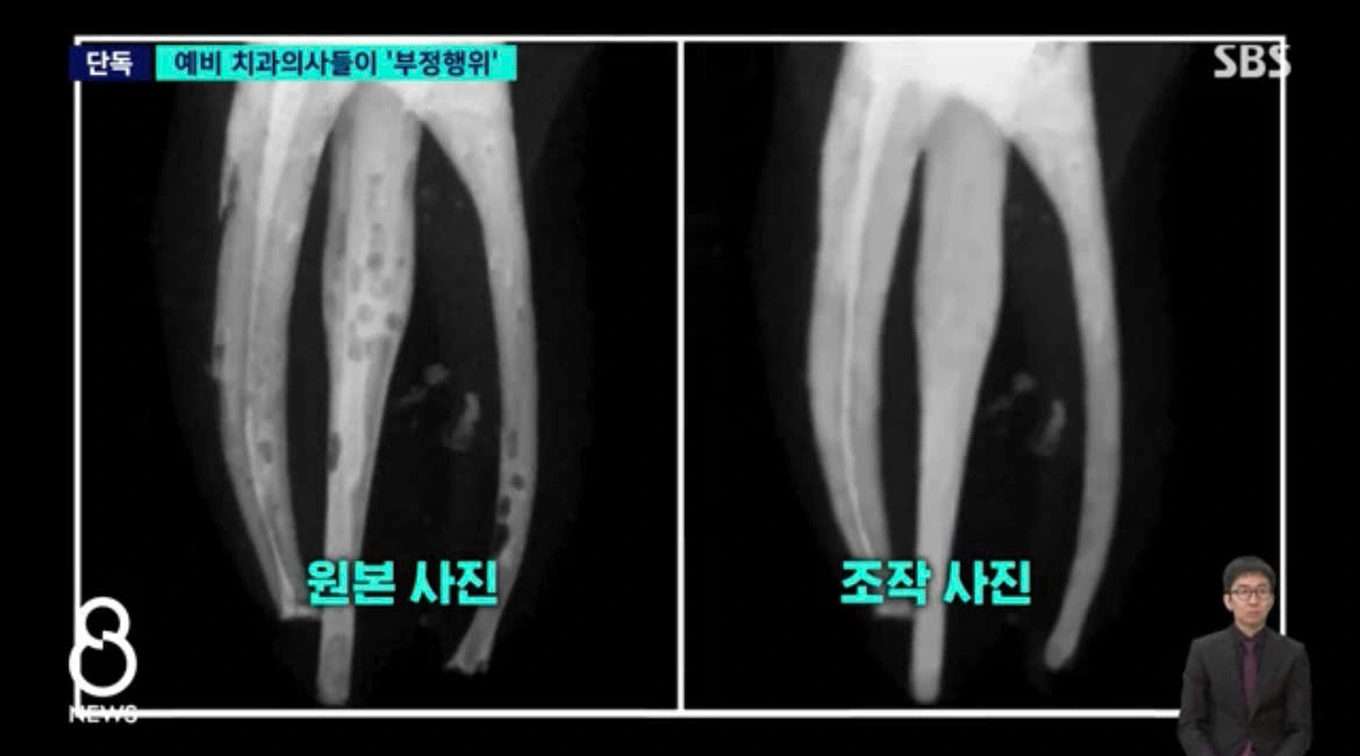

Đại học Yonsei (Hàn Quốc) vừa ghi nhận một vụ gian lận học thuật tập thể mới, khi 34/59 sinh viên năm thứ 4 khoa Răng Hàm Mặt bị phát hiện sử dụng Adobe Photoshop để chỉnh sửa ảnh X-quang trong bài thực hành. Những hình ảnh ban đầu cho thấy các bọt khí do trám tủy không đạt yêu cầu, nhưng trong bản nộp cuối cùng, các khuyết điểm này đã biến mất, khiến kết quả trông gần như hoàn hảo.

Qua xác minh, nhà trường xác định sinh viên đã chỉnh sửa hoặc sao chép hình ảnh của nhau để nộp bài. Đáng chú ý, các sinh viên này đều đang trong giai đoạn thực tập lâm sàng, được phép điều trị trực tiếp cho bệnh nhân dưới sự giám sát của giảng viên. Sau khi yêu cầu nộp lại ảnh gốc và bản tường trình, trường quyết định đình chỉ học tập 2 tuần đối với 5 sinh viên sao chép bài, trong khi 29 sinh viên chỉnh sửa ảnh phải lao động công ích 20 giờ.

Đại diện khoa Răng Hàm Mặt cho biết nhiều sinh viên chưa nhận thức đầy đủ mức độ nghiêm trọng của hành vi, do đây chỉ là bài tập không tính điểm. Trước đó, Đại học Yonsei cũng từng gây tranh cãi khi hơn 50 sinh viên bị phát hiện sử dụng AI tạo sinh để làm bài tập, cho thấy những thách thức ngày càng lớn trong việc kiểm soát gian lận học thuật trong bối cảnh công nghệ phát triển nhanh.